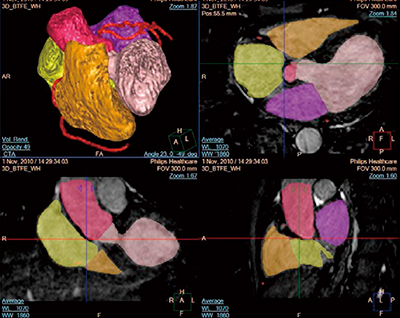

上記に示した解析ツールのほかに,最近搭載された新機能として“MR cardiac Whole Heart”“Advanced vessel analysis”がある。MR cardiac Whole Heartは,CMRAで取得したデータから目的とする心臓の解剖学的構造(大静脈,左室,左室心筋,左房,右室,右房,冠動脈)を自動分割する機能である(図5)。また,Advanced vessel analysisは,狭窄を認める動脈の狭窄率を2クリックで測定する機能である。これら新しい機能の追加により,多くの心疾患において臨床応用が期待されている。

図5 MR cardiac Whole Heartによる心臓解剖学的構造の分割